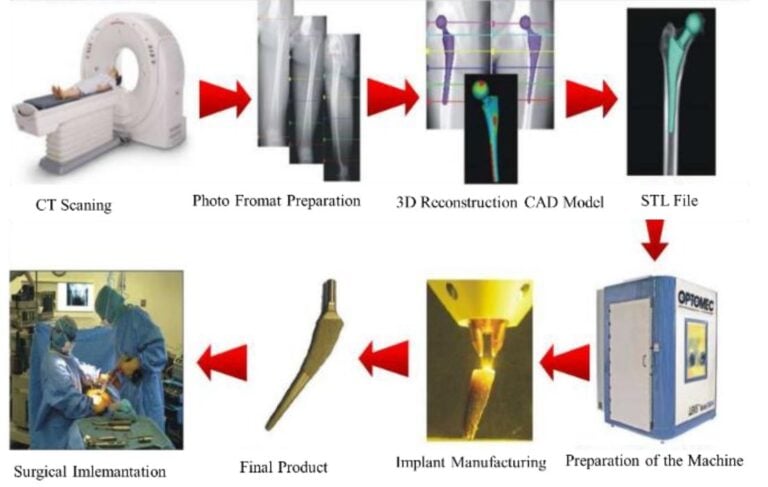

Orthopedic AM To Bioprinting: A 2030–2050 Outlook

A new academic roadmap lays out how orthopedic 3D printing could evolve into clinical bioprinting by 2050 — and what must happen along the way.

Prosthetic Printer Patent Targets Better Z Accuracy

A new Chinese utility model patent describes a compact high speed FFF 3D printer aimed specifically at prosthetic and orthotic manufacturing.